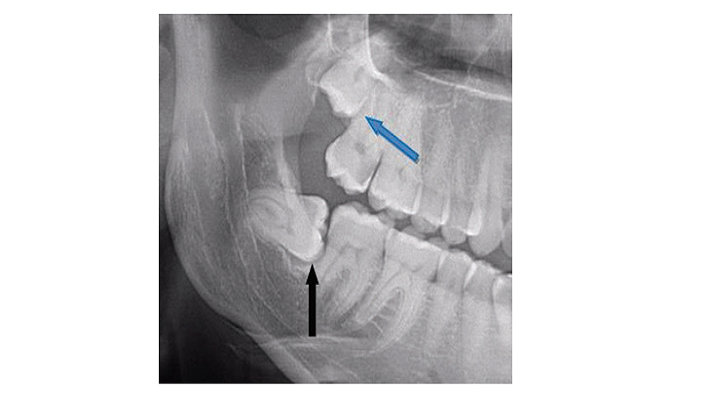

בתמונה: שן בינה שאובחנה אך לא נעקרה וכתוצאה מכך נגרם אובדן של שורש השן הסמוכה

בתמונה: היווצרות ציסטה סביב שן הבינה הכלואה